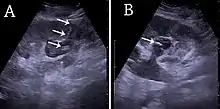

Figure 26. Acute pyelonephritis with increased cortical echogenicity and blurred delineation of the upper pole.[1]

Figure 27. Postoperative renal failure with increased cortical echogenicity and kidney size. Biopsy showed acute tubular necrosis.[1]